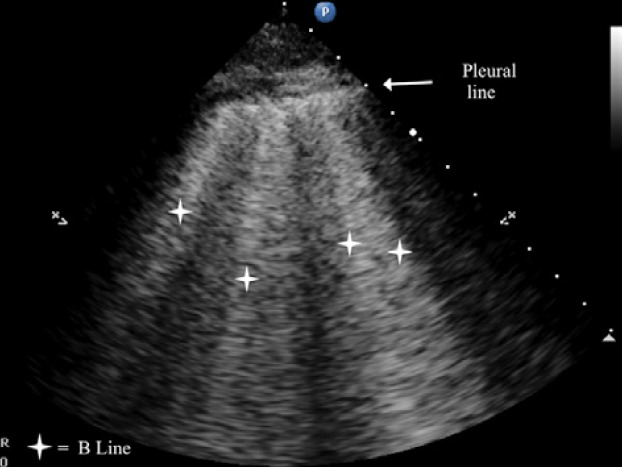

Abstract Image